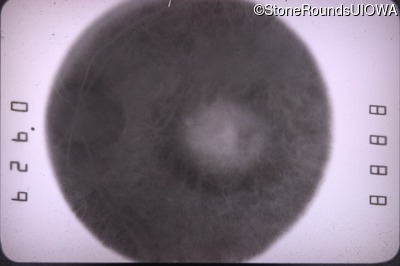

Infrared Fundus Photograph - Right - 20/60 -1

Exemplar